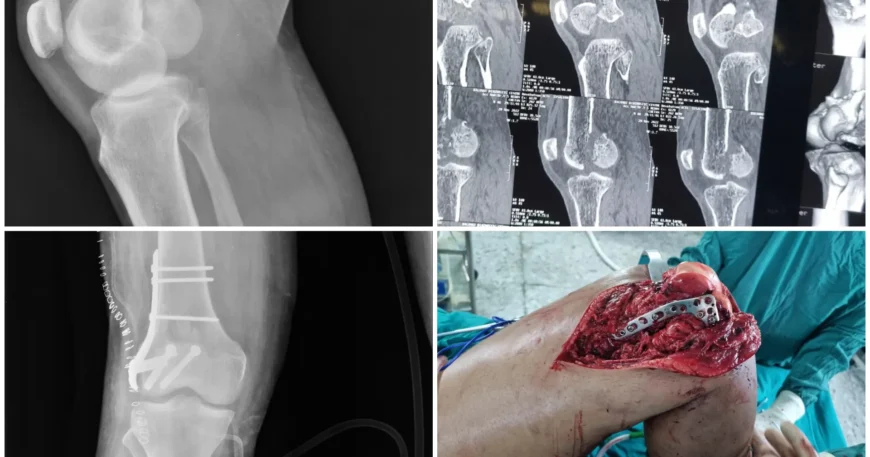

Clinical examination and imaging confirmed a Right Distal Femur Fracture with Hoffa’s fracture, a serious injury affecting the stability and alignment of the knee joint.

Mr. Chetan underwent Open Reduction and Internal Fixation (ORIF) using plates and screws to stabilize the distal femur fracture and restore proper alignment.

CC Screw Fixation for Hoffa’s Fragment

The Hoffa’s fragment was stabilized using CC (Cannulated Cancellous) screws, which provide:

This combined fixation ensured stable reconstruction of both the distal femur and the Hoffa fragment.